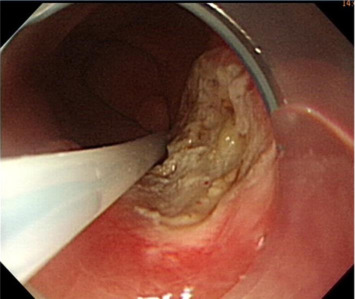

Initially, we administered a submucosal injection of diluted epinephrine along the margin of the larger lesion; however, we were unable to loop the snare around the lesion. A translucent plastic cap (straight distal attachment, MH-462, outer diameter 12.6 mm; Olympus, Tokyo, Japan) was first fixed on the tip of the endoscope and the cap was positioned on the target lesion. Suction was then applied to draw the flat lesion into the cap and, when the suction was released, the flat lesion became a pseudopolyp (Fig. 3 ). Next, we used an electrosurgical snare (oval shape, SD-9L-1, Olympus) to strangle the pseudopolyp immediately before when it became flat (Fig. 4 ). We then resected it with an electrosurgical generator (ERBE VIO 200D, settings with ENDO CUT Q model effect 3, duration 1, interval 5; Elektromedizin, Tübingen, Germany), resulting in an artificial ulcer without active bleeding or perforation (Fig. 5 ). We removed the smaller lesion smoothly by the same method and the total procedure time was 19 minutes. The patient fasted for 1 day and an intravenous proton pump inhibitor was given. Her course after EMR was uneventful and she was discharged 2 days later.

The elevation is immediately snared before it becomes flat and is removed using ...

Figure 4.

The elevation is immediately snared before it becomes flat and is removed using electrocauterization.